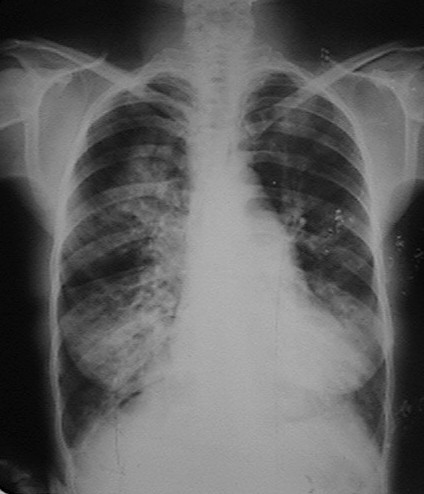

Fig.15a. 48 años. APP:  fumadora inveterada, asmática grado III, bronquiectasia. MC: fiebre 39oC, tos húmeda, expectoración blanquecina. EF: crepitantes en ambos campos, predominantes en bases. RX: Extensas lesiones inflamatorias en ambos campos asociadas a imágenes sugestivas de bronquiectasia. Aumento del diámetro vertical del tórax, descenso del diafragma. Convexidad del arco medio.

Fig.15b. RX evolutiva . Escasa mejoría. Se realiza ecocardiograma apreciándose aumento del diámetro de la arteria pulmonar y del VD con desplazamiento del SIV hacia la izquierda. Bronquiectasias infectadas.